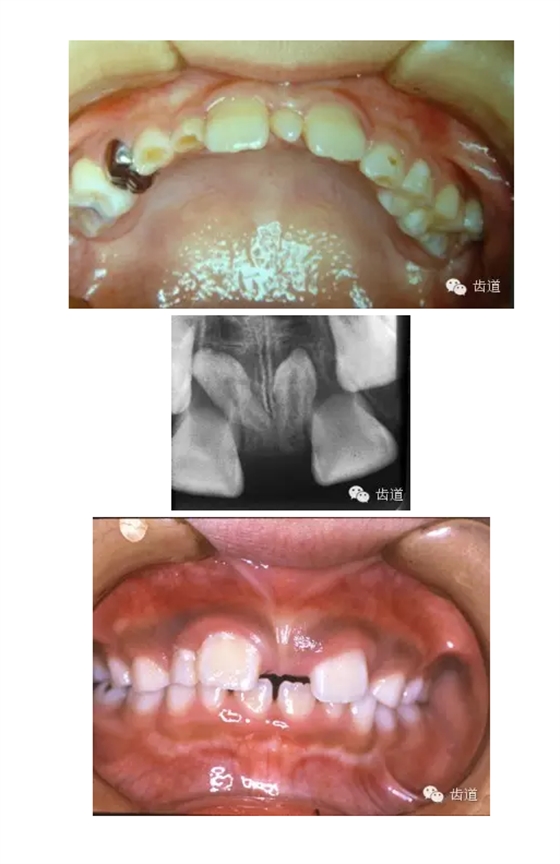

1.奶瓶齲:主要發(fā)生于上頜乳切牙的唇面,較快發(fā)展成廣泛性齲

2.環(huán)狀齲:乳前牙唇面、鄰面齲較快發(fā)展成圍繞牙冠的廣泛性的環(huán)狀齲,呈卷脫狀,多現(xiàn)于牙冠中部至牙頸部

3.猖獗性齲:把突然發(fā)生廣范圍快速的齲蝕,即使不易患齲的下頜乳前牙也受到齲蝕的侵蝕,而且隨著乳牙齲蝕很快發(fā)生牙髓感染的這類(lèi)齲蝕稱(chēng)為猖獗性齲。

乳牙齲病在臨床上表現(xiàn)為急性齲與慢性齲,濕性齲與干性齲